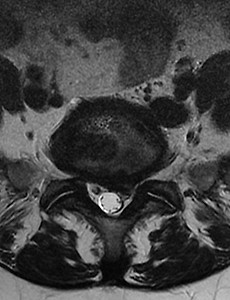

무릎통증, 무릎관절증! 따뜻한 봄이면 찾아오는 무릎통증, 무릎관절증! 날씨도 풀렸겠다 나들이를 가려고 했지만 ‘삐걱- 삐걱-‘ 하고 무릎이 고장 나버렸다! 따뜻한 봄과 함께 찾아온 무릎 통증, 벌써 나이가 든 걸까? 찌릿찌릿, 욱신거리는 무릎관절증에 대해서 알아보자.무릎관절증이란?무릎관절증이란 무릎에 염증이 발생하는 모든 질환을 일컫는다. 무릎관절증은 원인에 따라 ‘일차성’과 ‘이차성’으로 나뉜다. ‘일차성 무릎 관절증’은 무릎의 퇴행성 변화로 인해 연골, 뼈, 관절막에 변화가 나타나는 현상으로, 통증, 기능장애 등을 유발한다. 반면에 ‘이차성 무릎 관절증’은 세균성 관절염이나 결핵성 관절염처럼 질병으로 인해 관절 연골이 파괴되거나 심한 충격 등 외상으로 인해 발병된다. 일차성 무릎관절증은 ‘퇴행성 관절염’, ‘퇴행성 골관절염.. 2017. 5. 29.